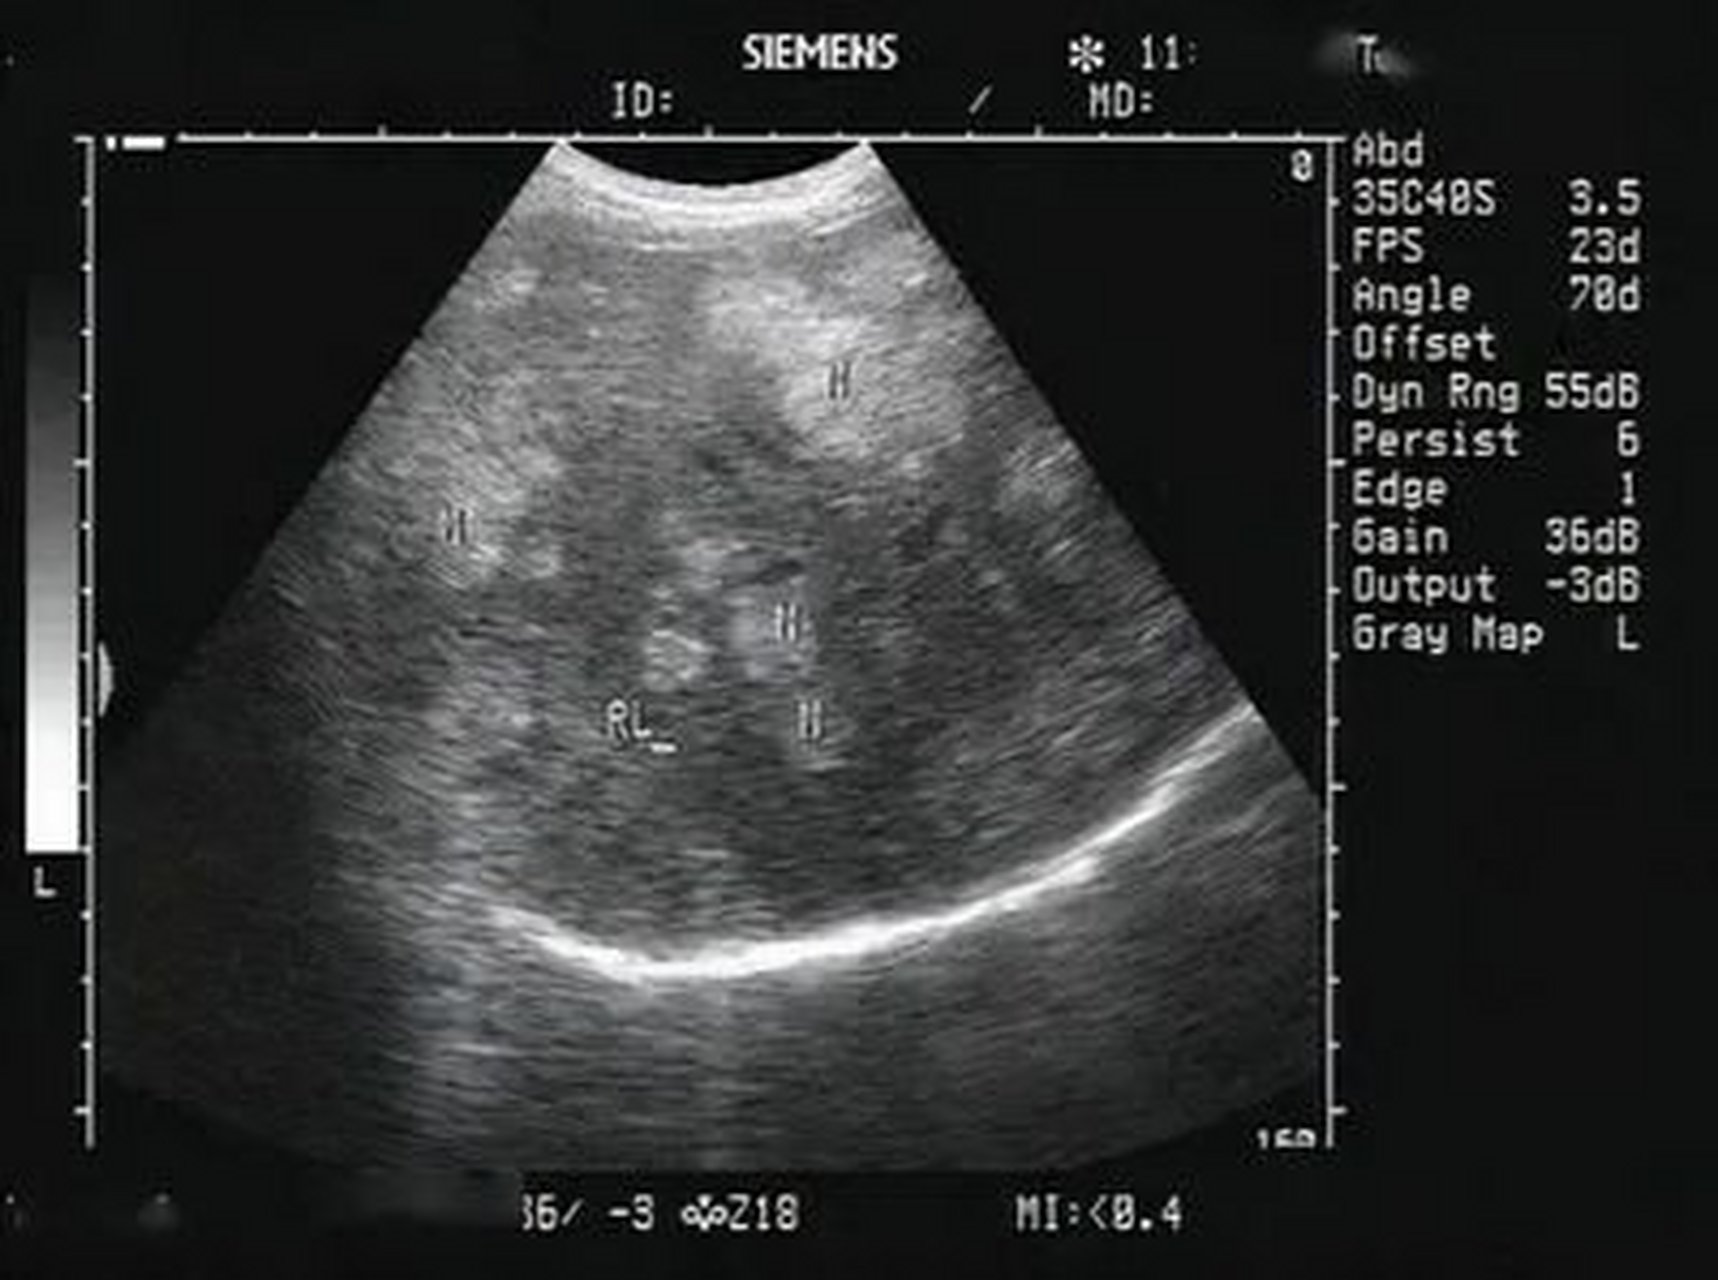

典型肝硬化 - 超声医学讨论版 - 爱爱医医学论坛

图片尺寸720x540